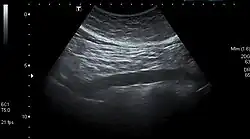

3. ^ Jang, Timothy (28 August 2017). "Bedside ultrasonography evaluation of abdominal aortic aneurysm—technique". Medscape.